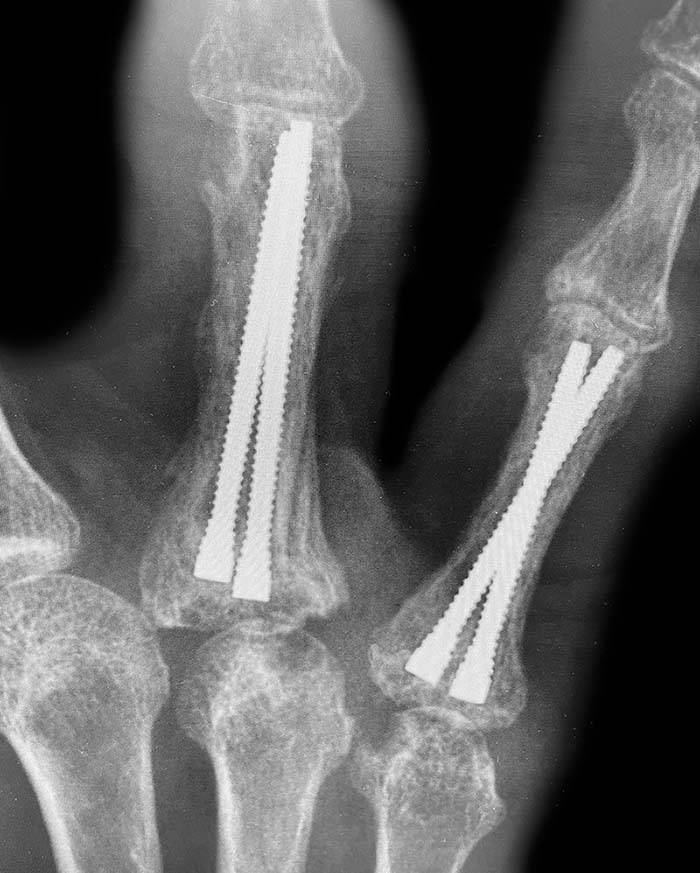

The InFrame Intramedullary Threaded Micro Nail system features a 2.0 mm diameter, stainless steel micro nail with a non-compressive design to achieve various implantation constructs for phalangeal fractures, providing superior rotational and bending stability and intramedullary fixation. The innovative delivery mechanism via the dual diameter guidewire eliminates the need for a dedicated reamer, simplifying a more precise implant placement.

The small 2.0 mm diameter, wide array of lengths, and unique delivery mechanism allow various implantation constructs to custom fit the intramedullary canal, generating greater rotational and bending stability and precise reduction for all types of phalangeal fractures.

• Multiple construct options. Small 2.0 mm diameter and wide array of lengths enable a more precise fit of the narrow intramedullary canal for enhanced stability of various phalangeal fracture patterns.